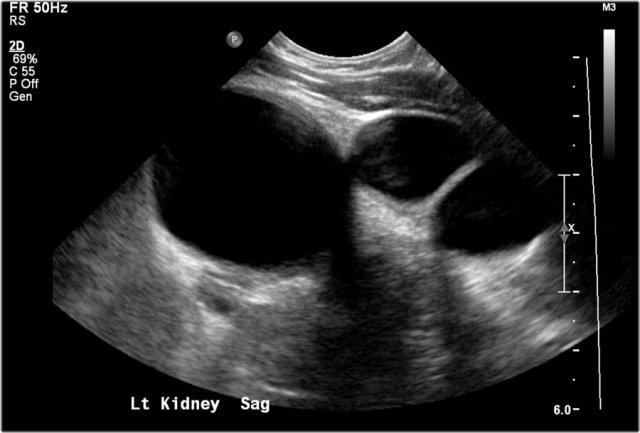

Here an ultrasound image of a five-month-old boy with an antenatally detected dilated pyelocalyceal system and no visible ureter, in accordance with a ureteropelvic junction stenosis.

On a sagittal image the dilated pyelocalyceal system is well seen.